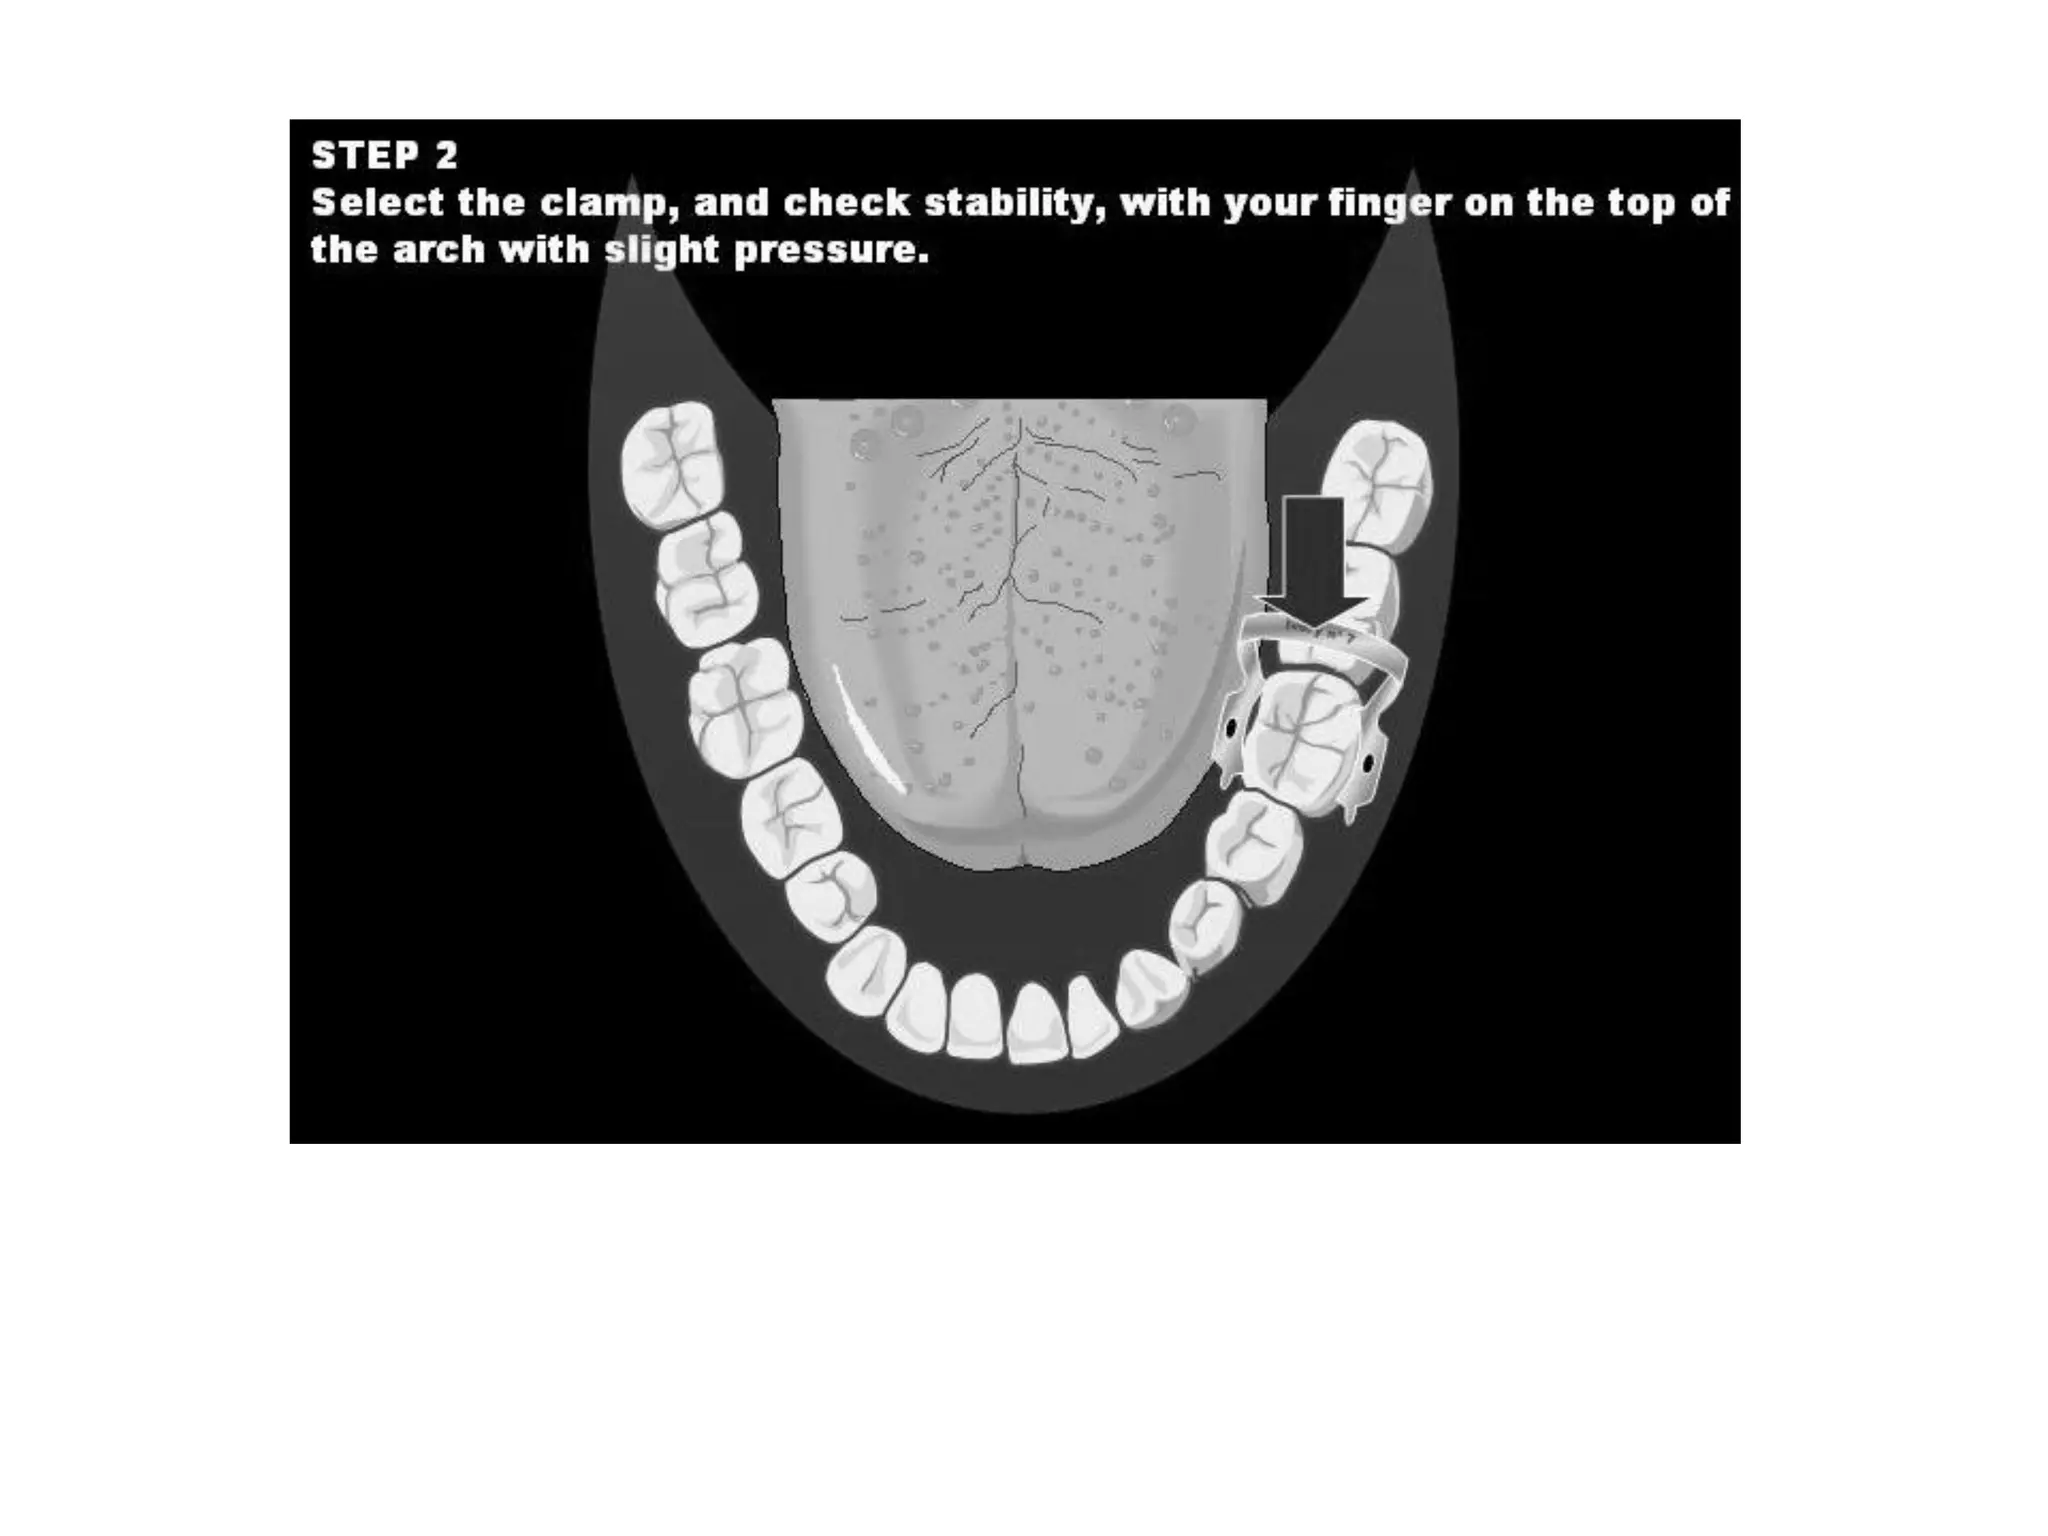

This document discusses the materials and components used for rubber dam isolation in dentistry. It describes the different types of rubber dam materials including color options and napkins to absorb moisture. It also outlines the tools needed such as punches to make holes, templates and stamps to guide hole placement, clamps to secure the dam, and other accessories like wedges and lubricant. Finally, it provides guidance on punching holes for different types of teeth and properly placing clamps in the rubber dam.